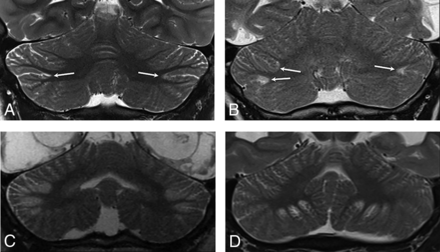

The key imaging feature was T2 and FLAIR hyperintensity and T1 hypointensity confined to the gray matter and immediate subjacent white matter at the depths of the cerebellar fissures (Fig 1). The findings were best seen on coronal and parasagittal fluid-sensitive sequences. In all patients, bilateral hemispheric involvement was present, with injury typically involving multiple fissures centered at the expected location of the borderzone between the superior cerebellar artery (SCA), AICA, and PICA (Fig 2). The cerebellar tonsils were injured in 39% (9/23) of cases. The cerebellar vermis was spared in 91% (21/23) of patients. Five of the 23 patients had prior imaging studies, all of which demonstrated a normal cerebellar cortex (Fig 3).

Coronal T2WI from patient 4 (A, C, and E) and patient 11 (B, D, and F) demonstrates the appearance of newly developed acute (C and D) and subsequent chronic (E and F) phase injury in previously normal cerebella (A and B). White arrows highlight multipe sites demonstrating progressive development of typical watershed injury in previously normal gray matter.

Imaging was available for 16/23 patients during the acute phase of injury, defined as <7 days from the suspected clinical event. All patients demonstrated normal thickness or a mildly thickened cerebellar cortex (Figs 3 and 4). Eighty-one percent (13/16) of patients demonstrated acute diffusion restriction (12 with an eventual clinical diagnosis of HII, 1 of unknown etiology) (Fig 4A–C), while 19% (3/16) of patients demonstrated no diffusion abnormality (all with an eventual clinical diagnosis of PRES) (Fig 4D–F). The 3 patients with PRES were imaged in the acute phase only, with no imaging follow-up available.